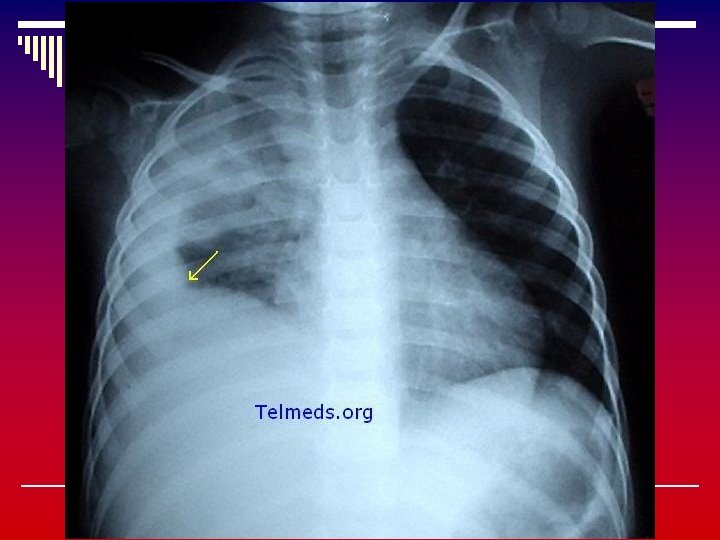

Junio 27 del 2006 Proceso fibrótico no neumónico